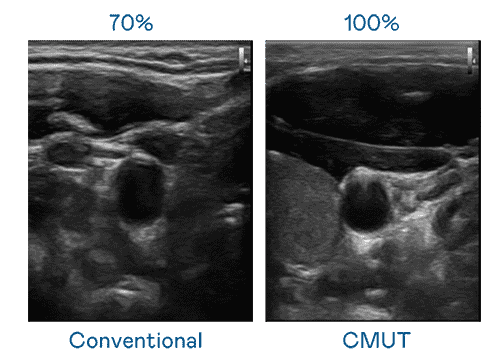

CMUT 技术是一种用电容式微机电元件来产生超音波讯号的技术。。。。与传统 PZT 压电式技术相比,,,CMUT 频宽增加 30%,,更宽频的超音波讯号让影像解析度大幅提升,,,是实现高影像品质医疗超音波扫描、、、、促进精准医疗发展的关键技术。。。。

超音波影像的解析度高低,,首先取决于探头能发出的讯号频宽。。。。巨星国际 CMUT 可提供高清晰的超音波讯号,,,,提供高频宽、、高灵敏度、、、影像纹理细节更高的超音波影像,,,,协助医护人员缩短影像判读时间及利用精准的医疗影像进行诊断。。。